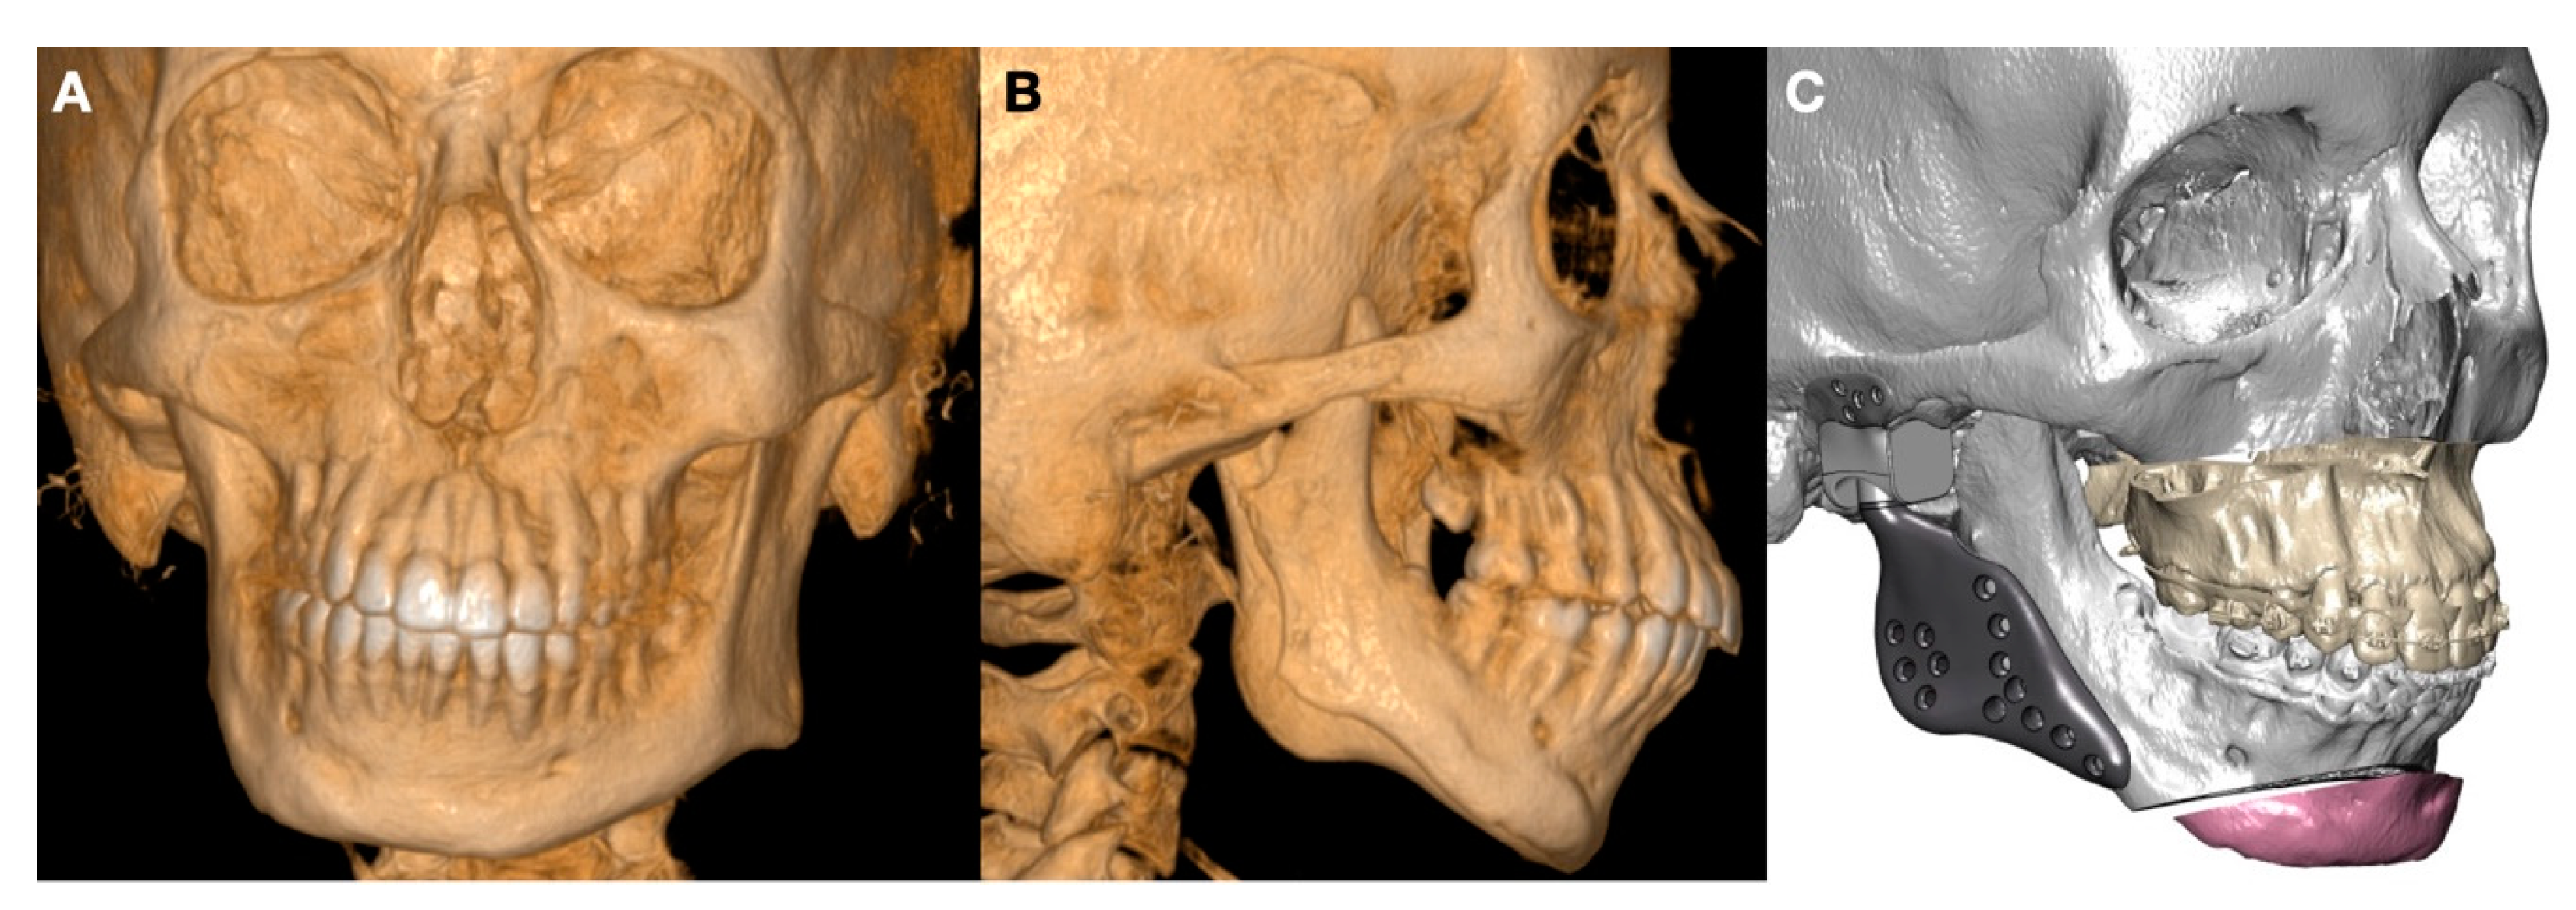

1.3. Clinical Conditions Related to Use of TMJ Replacement

- Volume and Size Augmentation of the Mandibular Condyle

- Volume and Size Reduction of the Mandibular Condyle

- Malformations, Pathology, or Trauma of the Mandibular Condyle